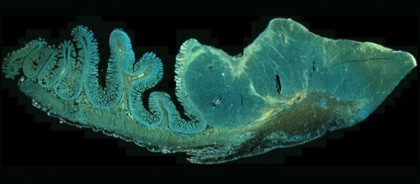

Practic, cercetătorii au prelevat biopsii de tumori (melanom în cazul de față) aflate în diferite stadii de dezvoltare în timpul terapiei. S-a măsurat apoi expresia proteinelor implicate în mecanismul cu rol în răspunsul adaptativ la tratament.

Metoda este uÈ™or de aplicat în tehnicile de rutină, precum imunohistochimia, făcând posibilă validarea in vivo a mecanismelor studiate, dar È™i impactul combinaÈ›iilor terapeutice inovatoare ce pot rezulta din înÈ›elegerea acestor mecanisme.

foto: SecÈ›iune analiză imunohistochimică metastază melanom intestinul subÈ›ire. © R.Merat, Neoplasia 2021; 23 (8): 775-782.